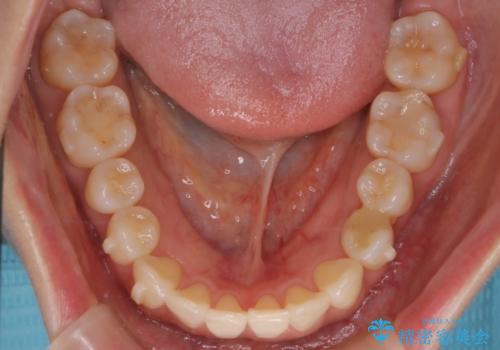

- インビザラインで非抜歯治療を行いました。IPRと拡大をし、叢生、咬合をきれいにしました。

主訴であったかみ合わせを正しい位置に動かし、バランスよくかめるようになりました。矯正治療終了後にメタルインレーをセラミックインレーに替えました。